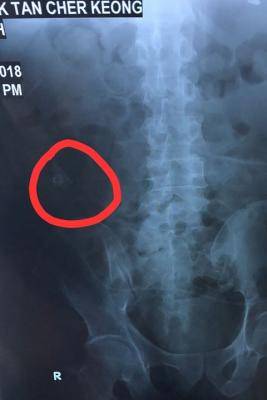

据家属向本报出示的医院报告和X光影像,陈志强的右腹有一个2.3公分大小的牙齿状实物。

X光照到陈志强肚子有牙齿状物体。(受访者提供)